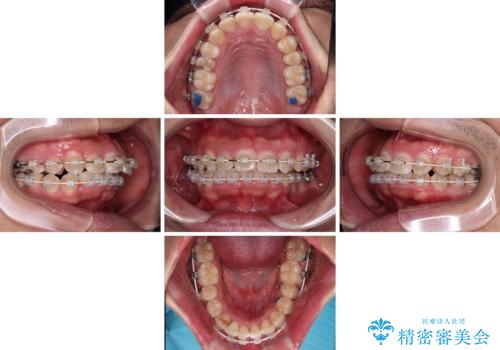

左右に顎がずれた咬み合わせ ワイヤー矯正で咬み合わせを改善

- デコボコと奥歯の咬み合わせのズレを気にして来院された患者様です。

骨格的に、下顎が右側にずれており、左側の咬み合わせに鋏状咬合などのアンバランスが生じている状態でした。

また、上顎前歯に欠損が1本あり、上下ともに前歯部に叢生が認められ、下顎前歯の大半が隠れてしまうほどの過蓋咬合も認められました。

咬合平面を平坦にしながら前歯の咬み合わせを挙上し、デコボコと鋏状咬合も改善していくこととしました。

骨格的な左右差が大きかったため、上下の正中のズレや、左右奥歯の咬み合わせなどは妥協的な仕上がりとなりました。

骨格的なズレに対応するにはワイヤー矯正が至適であり、マウスピース矯正は選択しないようにお話をしました。